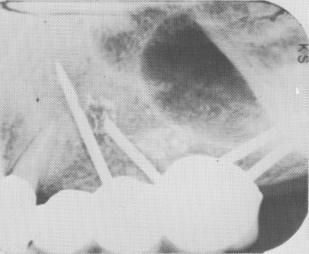

Fig. 7-108. A periapical radiograph showing the shortened pin. The probem has now been eliminated and the implant is secured.

2 Radiograph of shortened upper endosseous pin implant, problem resolved